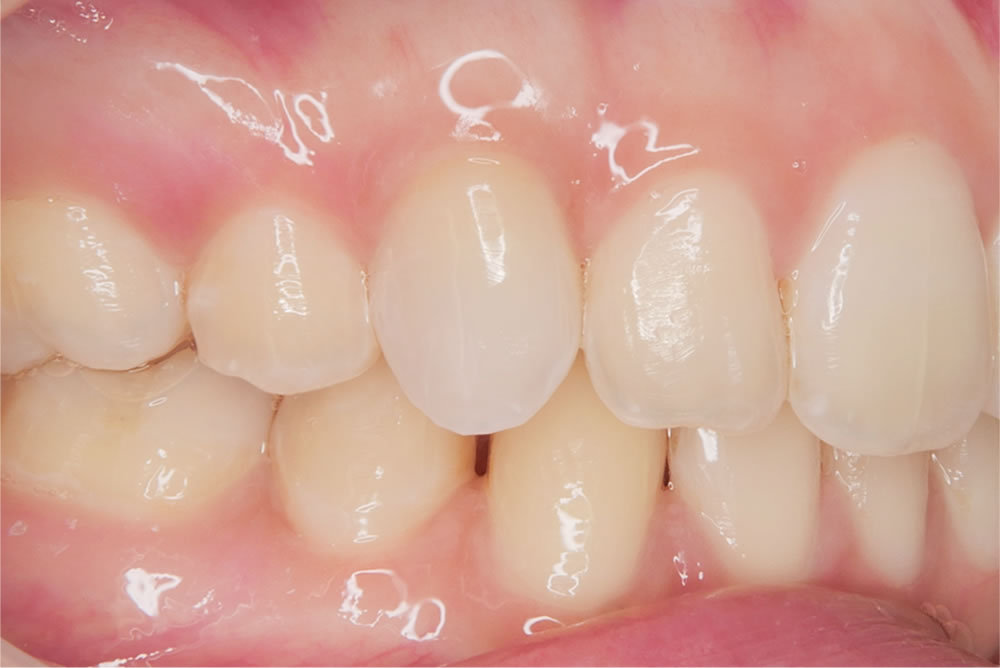

神経を失い黒ずんだ前歯を削らずに耐久性と審美性を回復した症例

こちらの患者さんは、右上の前歯の色が黒くなってきたことを主訴に来院されました。

写真の通り、この歯だけが変色しており、他院では「削って被せ物にする必要があるかもしれない」と説明を受けていたそうです。

当院ではまず原因を調べるために各種検査を行いました。その結果、右上の前歯は冷たい刺激に反応せず、神経が死んでしまっている(失活歯)と判断しました。